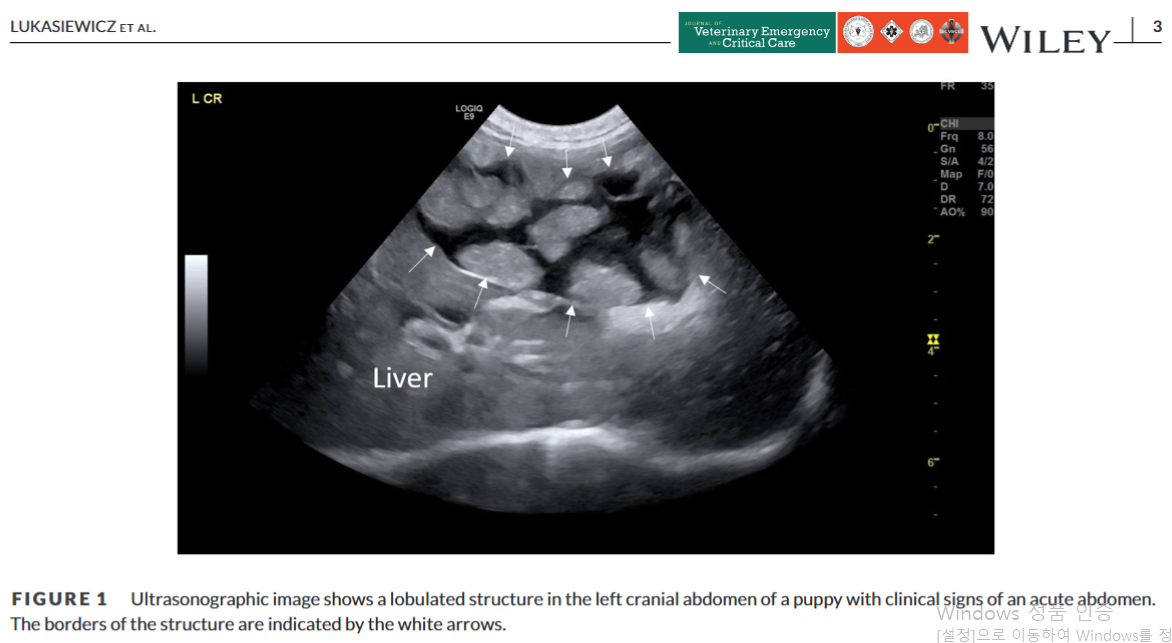

이번에는 췌장영전 케이스가 보고되어 소개한다.